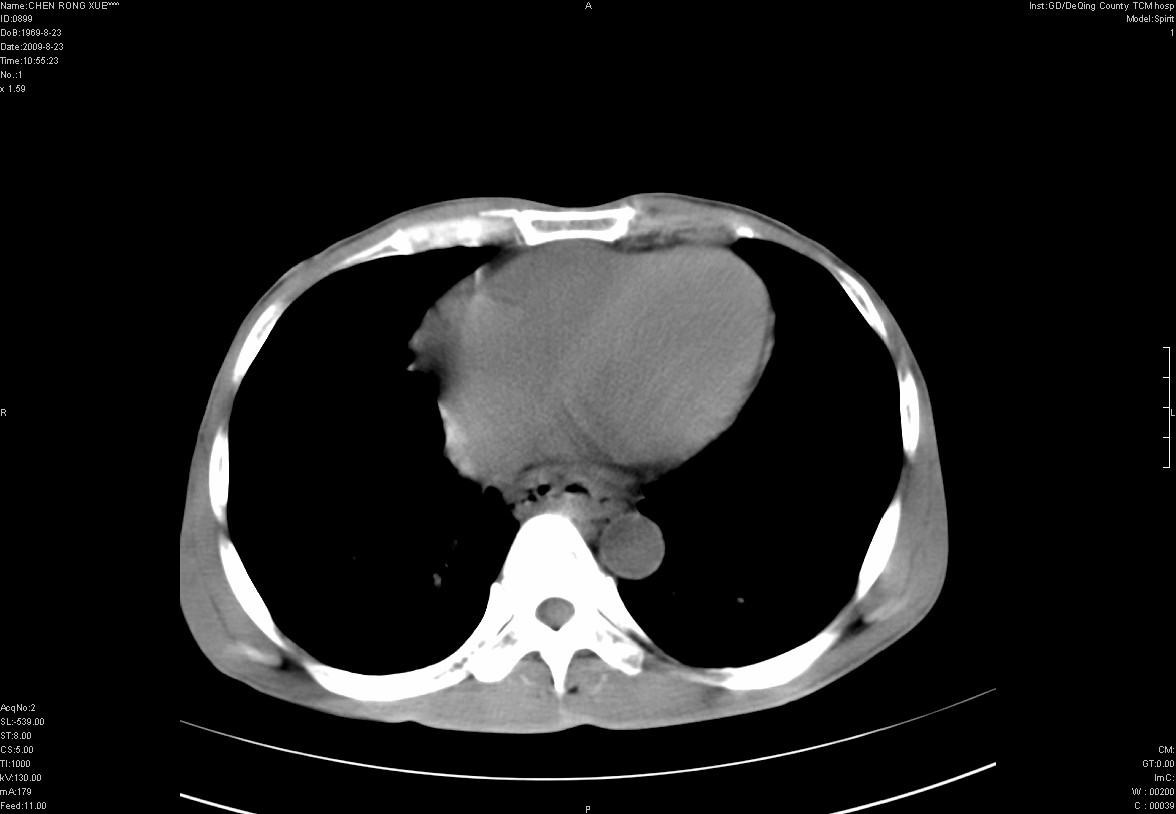

以下是引用zxl51642在2009-8-23 12:56:00的发言:[br]1、肝硬化、脾大;2、慢性胆囊炎;3、右肾占位并右侧腰大肌受侵,考虑恶性可能性大,建议增强扫描进一步检查。

以下是引用qiuleiyu在2009-8-23 15:17:00的发言:[br]1、慢性肝病,肝硬化,脾大,门脉高压。胆囊小结石。[br]2、右肾明显肿大,伴片状低密度灶,累及右侧腰大肌,肿瘤及炎症性病变皆有可能大,建议增强。

以下是引用zjzjr在2009-8-23 17:42:00的发言:[br]1、慢性肝病,肝硬化,脾大,门脉高压。胆囊小结石。[br]右肾脓肿波及肾周,建议增强